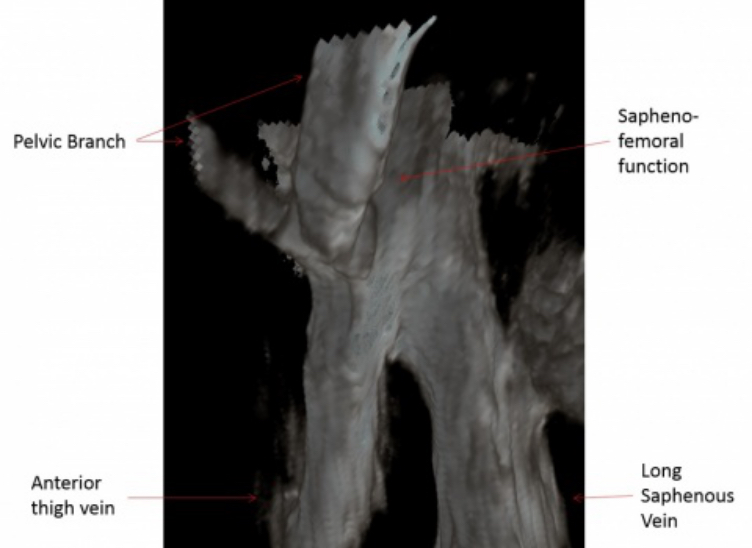

Mindray'in Resona 7 ürünü ve bu üründeki gelişmiş kan akışı saptama özellikleriyle birlikte, Piur Imaging'in tomografik ultrason cihazının desteğiyle araştırmacılar, son derece doğru ve ayrıntılı bir 3B tomografik görüntü oluşturabilir. Bu, vücudun atardamarlarının, toplardamarlarının ve kan damarlarının bir tür 3B haritasını oluşturmaktadır. Resona 7'nin ileri düzey teknolojileri ve kristal netliğinde görüntü kalitesi sayesinde bu ürün, araştırmacılar tarafından, vücudun çoğu bölgesinde arteriyel ve venöz hastalıkların incelenmesi için zaten ilk tercih olarak kabul edilmişti. Ancak Mindray'in Ar-Ge ekibinin yardımıyla araştırmacılar bir adım daha ileri giderek vasküler bir 3B tomografik ultrason görüntüsüyle ilgili fikirlerini sağlamlaştırabildi.

3B Tomografik Ultrason Görüntüsü. Resim, healthcare-in-europe.com web sitesinin izniyle alınmıştır

Vasküler 3B tomografik ultrason görüntüsüyle doktorlar, bir atardamara, toplardamara veya kan damarına, her açıdan ve hatta içeriden istedikleri gibi bakabilir. Doktorlar, pek çok açıdan ve perspektiften bakabildiklerinde, doğru bir analiz yapabilir ve plak birikimini incelerken ölçümler yapabilir. Plak birikimi olduğunu saptarlarsa, birikimin hacmini analiz edebilir ve bulguları temelinde güvenli tedavi ve hatta, felç müdahale seçenekleri gibi cerrahi kararlar verebilirler.

Ekip şu anda, anevrizma taramasının doğruluğunu geliştirmeye çalışmak üzere aynı tekniği kullanmanın yanı sıra, analizin bu yönüne yoğun bir şekilde odaklanıyor.

Plak hacminin, felç semptomlarıyla çok önemli bir ilişkisi olduğunu saptadık. Felç riski %5’ten fazlaysa, karotid plakları olan kişileri saptamak için, popülasyon taraması yapılması yararlı hale geliyor. Plak hacmini ölçmek için, Resona 7 tomografik ultrason çözümünü kullanabiliriz.

3B Tomografik Ultrason Görüntülemede Resona 7'nin Rolü

Resona 7’deki gelişmiş teknolojiler sayesinde, 3B tomografik görüntüleme yapılabilmektedir. Mindray’in V Flow teknolojisini içeren Resona 7, taranan atardamar, toplardamar veya kan damarı içindeki kan hücrelerinin hız büyüklüğünü ve yönünü doğru bir şekilde gösterebilir.

Yeni 3B tomografik ultrason görüntüleme, damar hastalıklarını analiz etmek ve anevrizmaları ölçmek için en çok tercih edilen yöntemlerden biri olma potansiyeline sahiptir.